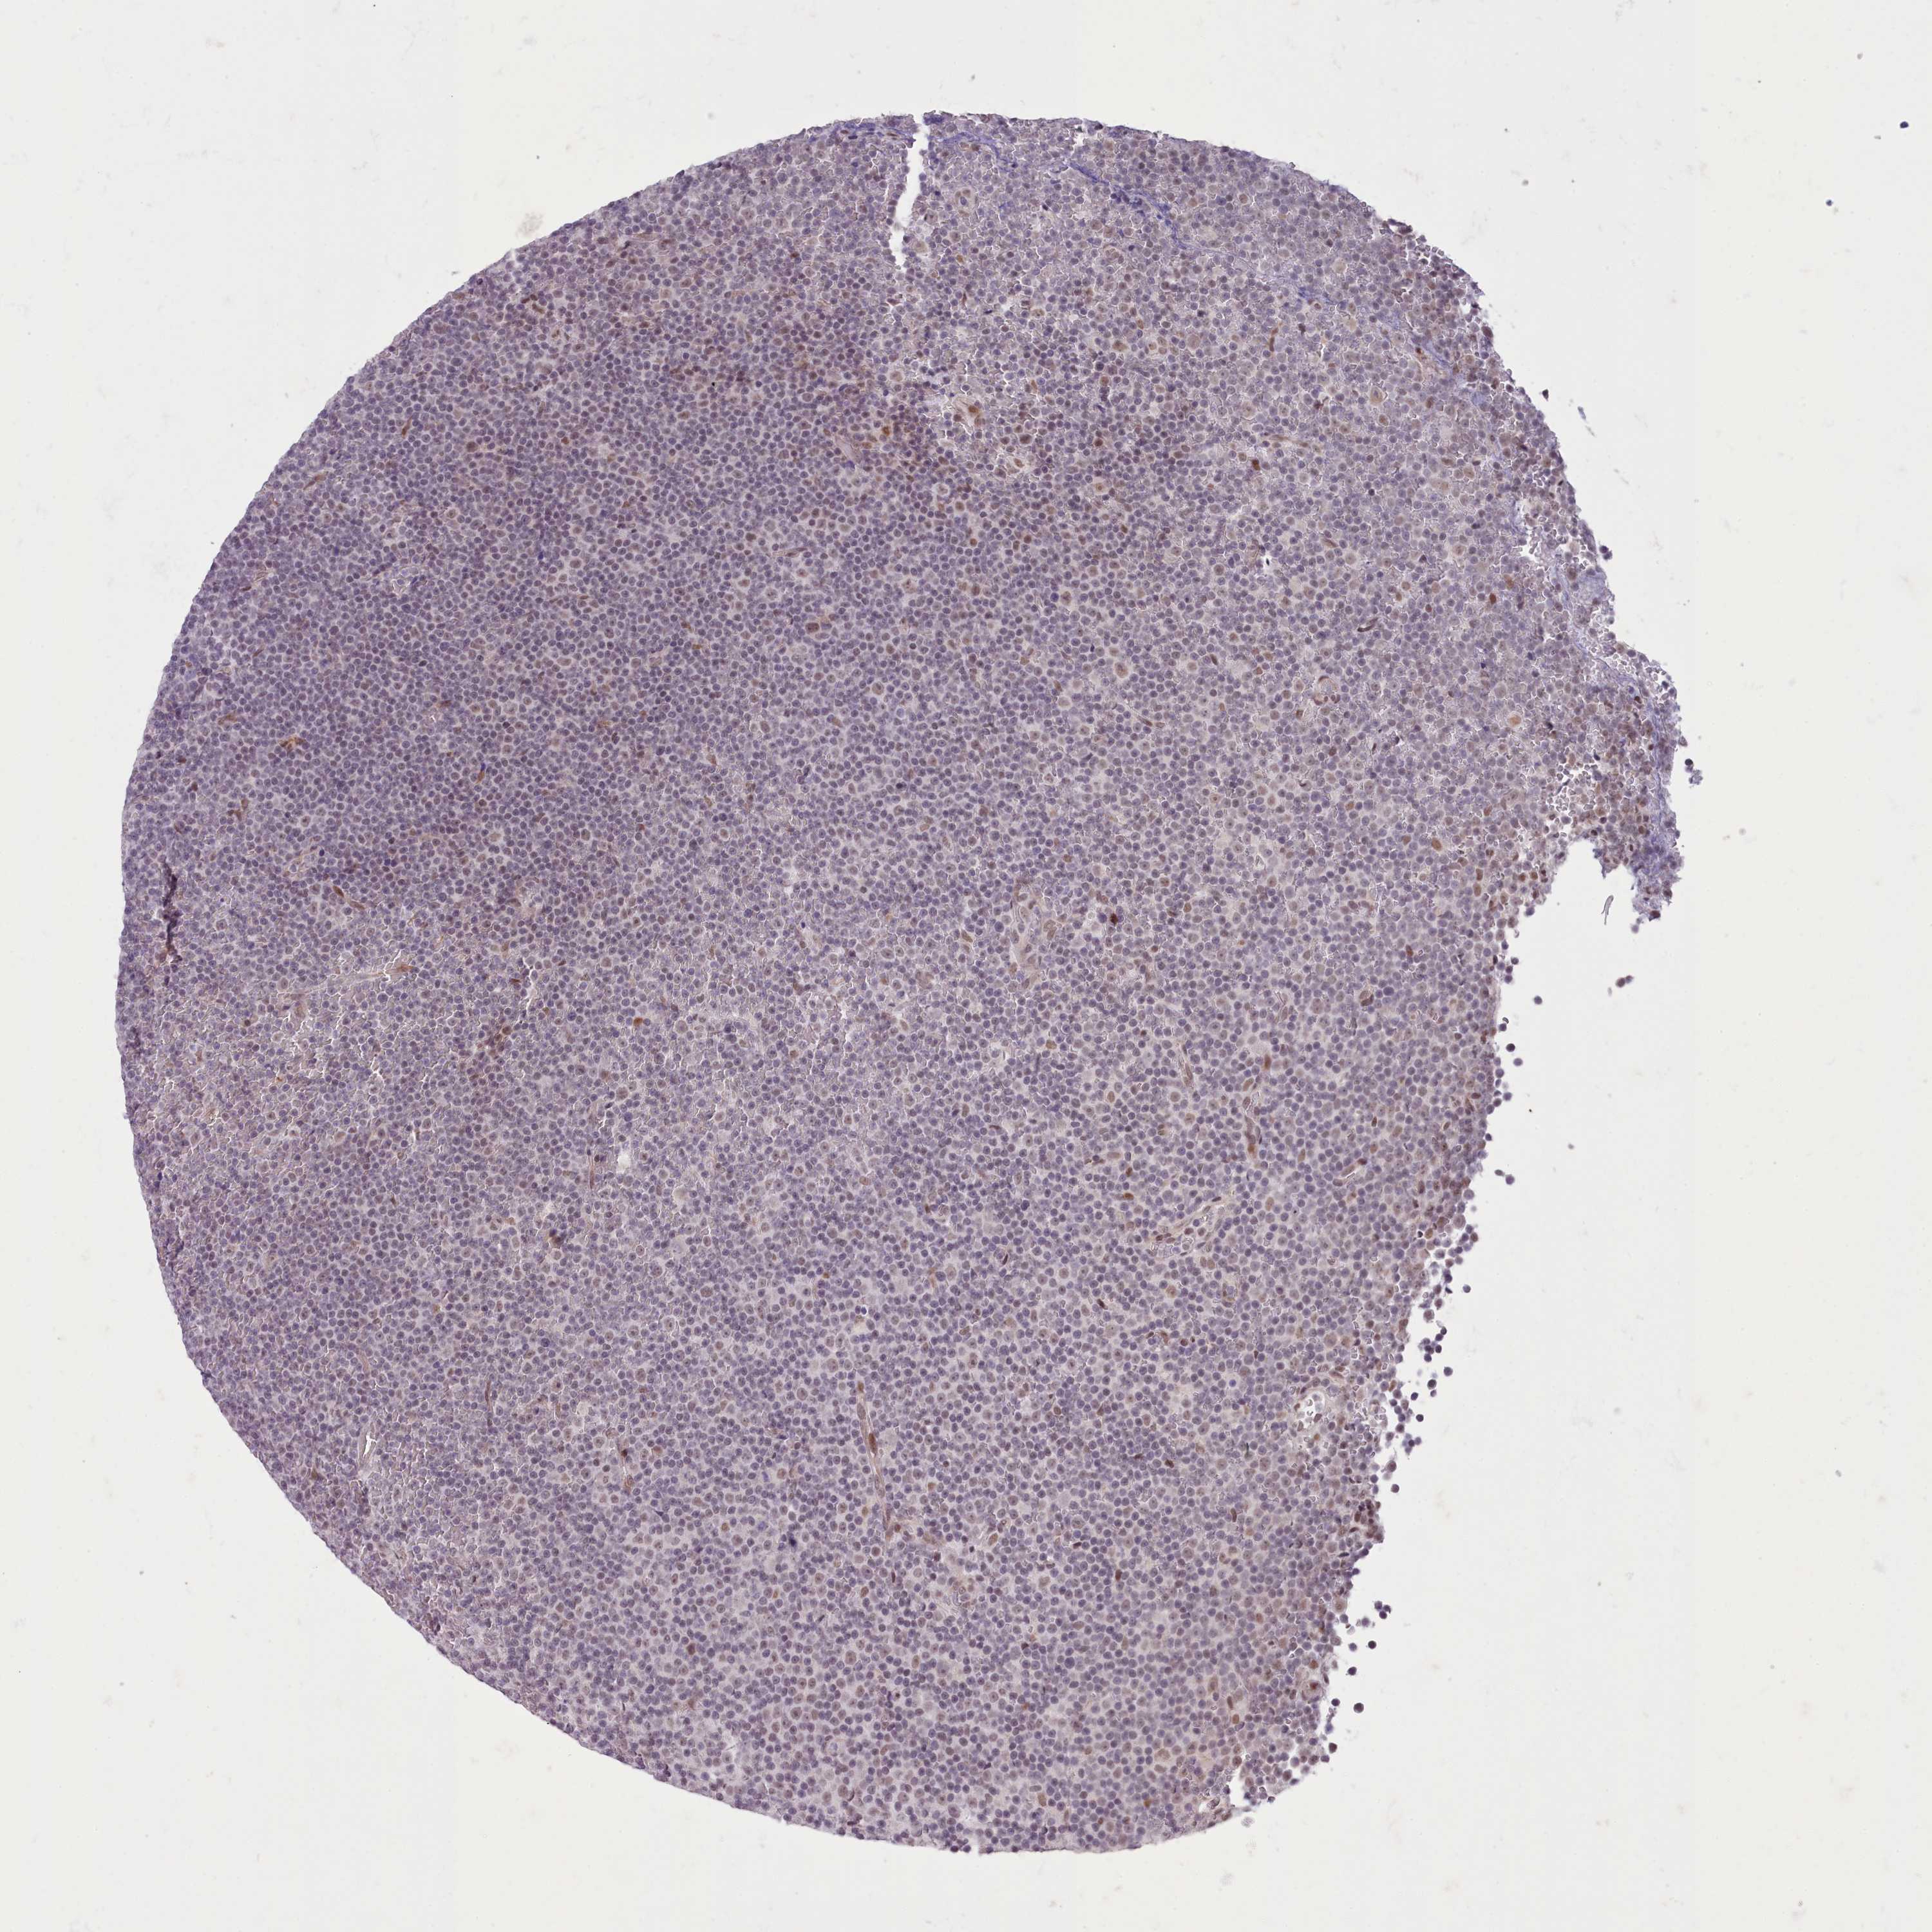

CANCER LYMPHOMA Show tissue menu

LYMPHOMA - Protein expressioni

A mouse-over function shows sample information and annotation data. Click on an image to view it in a full screen mode. Samples can be filtered based on level of antibody staining by selecting one or several of the following categories: high, medium, low and not detected. The assay and annotation is described here.

Each image is clickable and will lead to virtual microscopy that enables deeper exploration of all samples and also displays staining intensity scores, fraction scores and subcellular localization as well as patient and tissue information for each sample.

Antibody HPA048722

Hodgkin's disease, NOS

Malignant lymphoma, non-Hodgkin's type, High grade

Malignant lymphoma, non-Hodgkin's type, Low grade